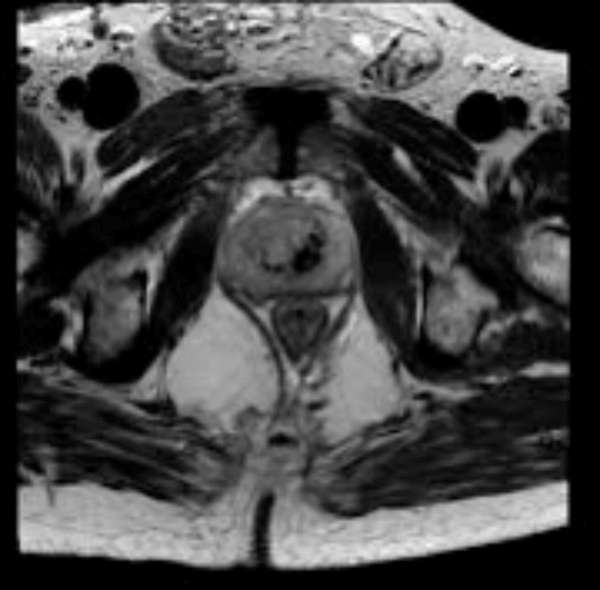

These are a series of radiological images highlighting serious urological infections.

A.

B.

C.

- What are the radiological diagnoses from these images?

Case 3

-

a: emphysematous prostatitis

b: emphysematous cystitis

c: emphysematous pyelonephritis.

Recent instrumentation, fistula from genitourinary tract, trauma, infarctions (spontaneous / elective), urinary diversions, infections.

e.coli, candida, klebsiella, proteus. These organisms can cause sugar fermentation and release of carbon dioxide.

Huang-Tseng CT classification:

Class 1: gas in collecting system

Class 2: gas in parenchyma

Class 3a: extension of gas into perinephric space

Class 3b: extension of gas into pararenal space

Class 4: Bilateral or solitary kidney.